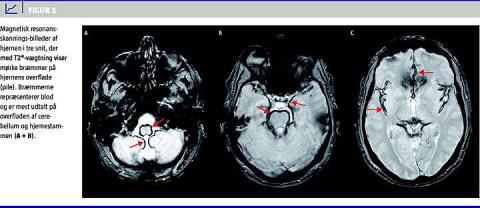

Der blev udført en magnetisk resonans (MR)-skanning af cerebrum. På standardsekvenserne fandt man normale forhold, men med T2*-vægtning blev der set »mørke bræmmer« på hjernens overflade, mest udtalt omkring hjernestammen og den øvre del af vermis (Figur 1 ). Patienten fik derfor diagnosen SS. Paraklinisk var cerebrospinalvæsken (CSV) positiv for xantokromi, der var 505 mio. erytrocytter/l, protein på 0,79 g/l og 10 mio. leukocytter/l. Der var ingen bakterier eller virus i CSV, og blodprøverne var normale.

Diagnosen stilles ved MR-skanning af cerebrum, der på billeder med T2*-vægtede skanninger viser hypodense randzoner omkring cerebellum, hjernestammen og evt. langs kortikale fissurer, rygmarv og nerverødder. Ofte ses et øget antal blodlegemer samt protein og xantokromi i CSV.